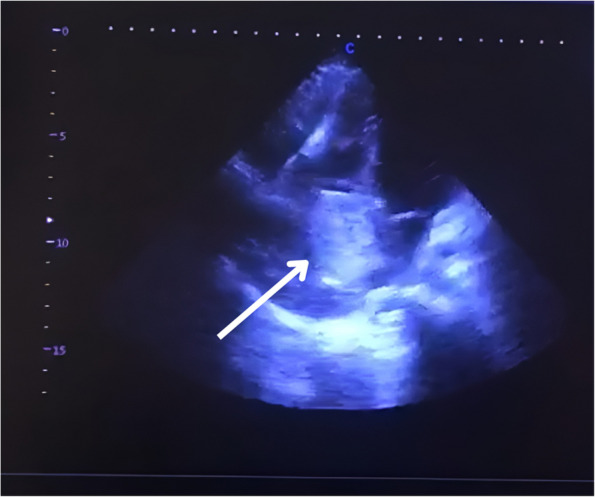

心房黏液瘤是最常见的原发性心脏肿瘤。20%的病例起源于右心房。据报道,只有少数此类肿瘤起源于下腔静脉。我们报告一例20岁女性复发性呕吐和室上心动过速(SVT),发现有一个巨大的黏液瘤出现在肝上下腔静脉(IVC),累及咽鼓管瓣膜,并延伸到右心房。手术切除是成功的,导致平静的恢复。本病例强调了及时诊断和手术干预治疗右心房黏液瘤的重要性,以防止潜在的并发症,如栓塞和猝死。

Atrial myxomas are the most common primary cardiac tumors. In 20% of cases, they arise from the right atrium. Only a few such tumors are reported to have arisen from the inferior vena cava. We present the case of a 20-year-old female with recurrent vomiting and supraventricular tachycardia (SVT), found to have a massive myxoma emerging from the suprahepatic Inferior vena cava (IVC) involving the eustachian valve, and extending to the right atrium. Surgical excision was successful, leading to an uneventful recovery. This case underscores the importance of prompt diagnosis and surgical intervention in managing right atrial myxomas to prevent potential complications such as embolism and sudden death.